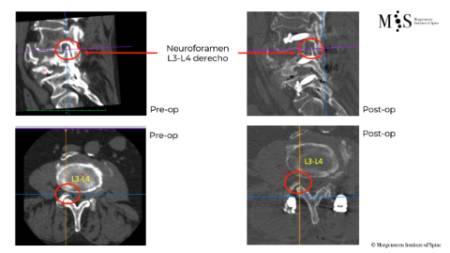

Estabilització percutània de fractures vertebrals inestables

En casos de fractures vertebrals complexes, inestables, comminutes, etc. es requereix una estabilització addicional de la fractura mitjançant una artròdesi percutània, i en alguns casos en els quals hi ha compromís neurològic, una descompressió del canal medul·lar. L’artrodesi percutània permet estabilitzar l’estructura compromesa de la columna vertebral i descarregar la càrrega del pacient sobre la fractura. Addicionalment se solen cementar les vertebres artròdesis i la fractura vertebral mitjançant cifoplastia.

Fractura Vertebral Ejemplo de Caso Clínico